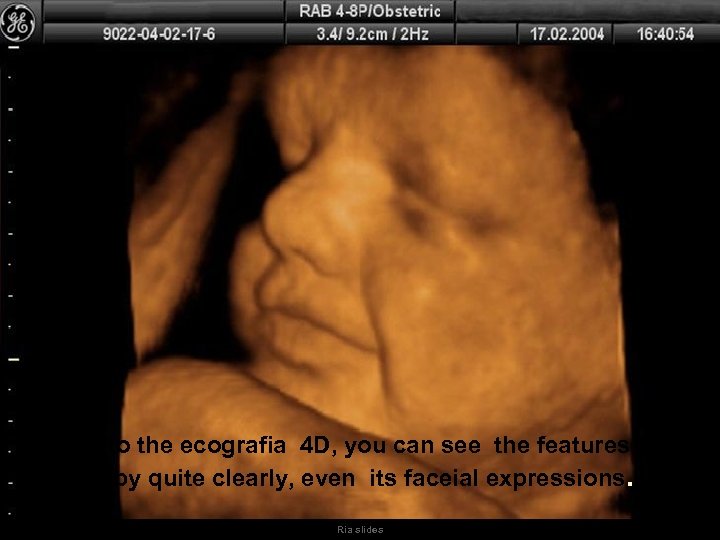

Thanks to the ecografia 4 D, you can see the features of the baby quite clearly, even its faceial expressions. Ria slides